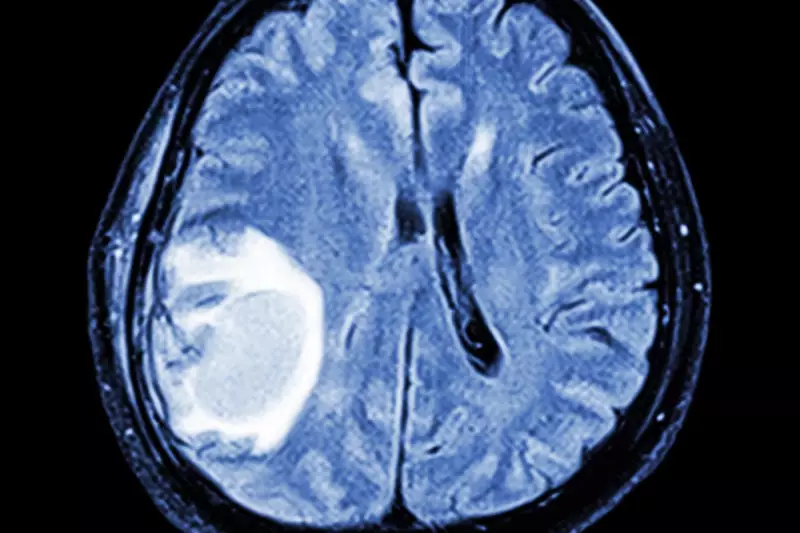

Early diagnosis significantly improves treatment outcomes for brain tumour patients. With over 12,000 people diagnosed with brain tumours annually in the UK, recognising the full range of symptoms becomes crucial for timely intervention.